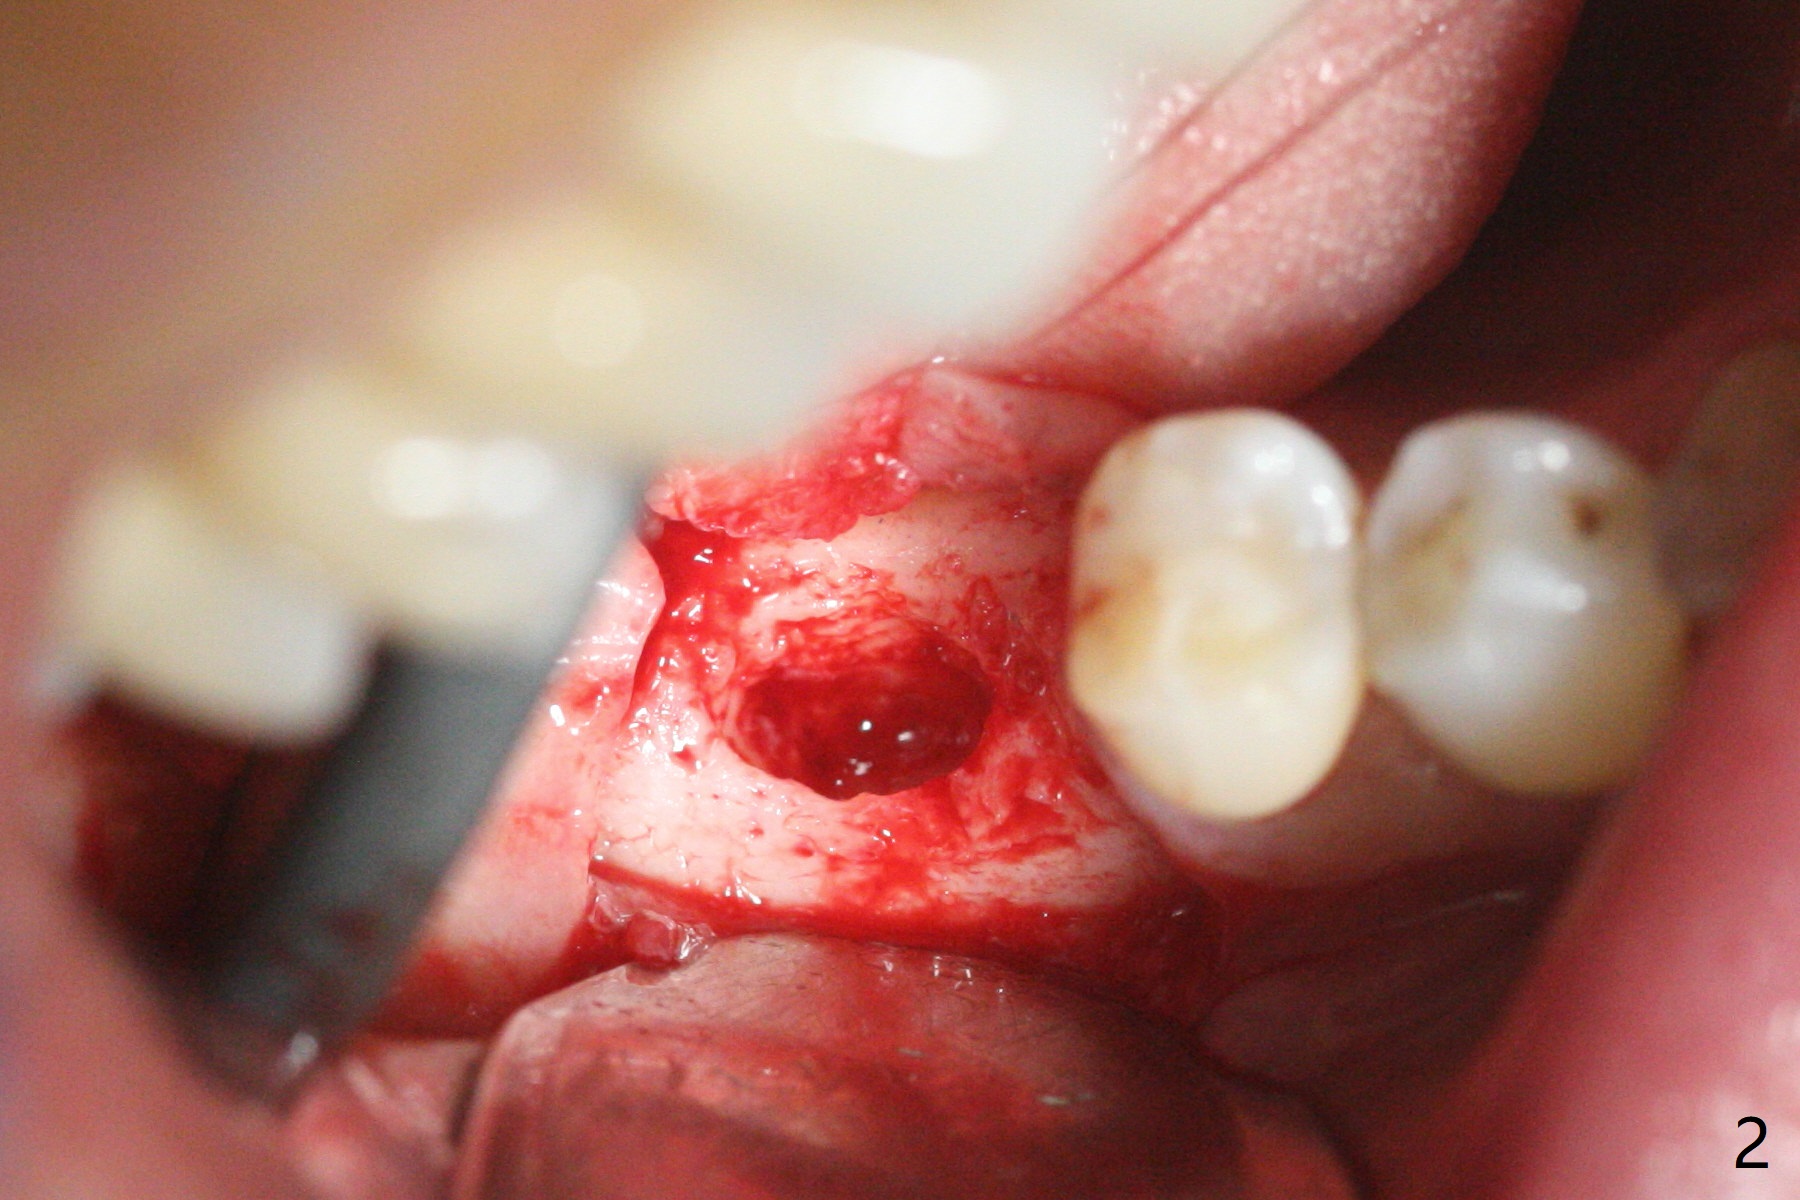

74岁女,右下6因植牙周围炎,植体取出,植骨,术后14个月回来做导板植牙术,局部infiltration时,发现位点中央有些分泌物,刮匙证实有一个瘘道(图一),翻瓣似乎不可避免,骨质缺损没有完全愈合(图二),其实仔细温习术前CT也能发现缺损(图三),导板钻洞位于缺损近中(图四:白圆圈),随着钻头直径增大,钻洞会偏移远中(图四:箭头)和颊侧(由于舌侧骨板厚,颊侧骨板低)。因此用过4毫米钻头后,植入4毫米报废IS植体,接近颊侧。同时为了防止植体断裂,选择五级钛植体(图五)。由于扭力低(手植入,有间隙:图五:<),包埋,使用自体骨和异体骨(皮质,*)。覆盖Osteogen tape后,PGA缝合,牙周胶水(图六)。如果植入4.5毫米植体,后者会更偏移远中。